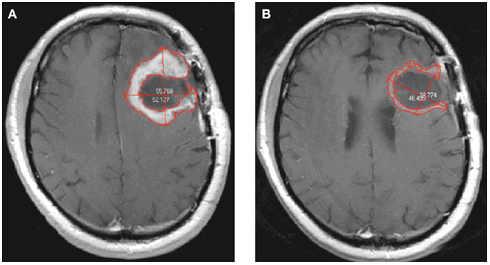

Εφικτή η διάγνωση του καρκίνου εγκεφάλου πέντε χρόνια πριν την εμφάνιση συμπτωμάτων

Η αλληλεπίδραση μεταξύ των πρωτεϊνών που μεταδίδουν πληροφορίες από το ένα ανοσο-κύτταρο στο άλλο είναι αποδυναμωμένη στο αίμα των πασχόντων από καρκίνο του εγκεφάλου ήδη πέντε χρόνια πριν από την διάγνωση του καρκίνου, ανακάλυψαν αμερικανοί ερευνητές.